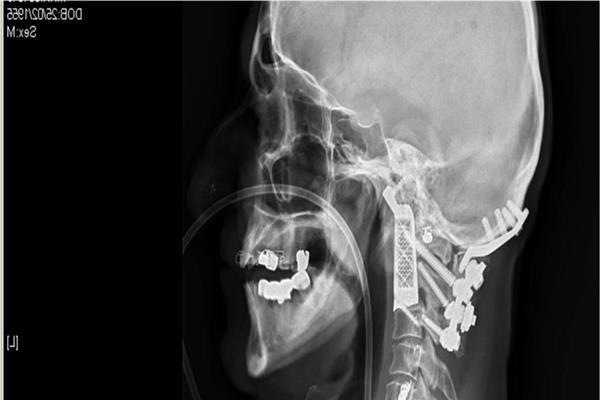

面對(duì)一臺(tái)風(fēng)險(xiǎn)如此高的手術(shù),醫(yī)生進(jìn)行了周密的手術(shù)預(yù)規(guī)劃。***終確定的手術(shù)方案是從病人嘴部進(jìn)入,切除腫瘤以及頭頸部的兩節(jié)脊椎,隨后植入鈦金屬3D打印脊椎。3D打印脊椎植入物是根據(jù)病人的身體和手術(shù)切除方案進(jìn)行設(shè)計(jì)的,與進(jìn)行過(guò)腫瘤和脊椎切除后的部位可以進(jìn)行完美的匹配。者在術(shù)后的2個(gè)月中恢復(fù)順利。目前,他的脖子已經(jīng)可以活動(dòng),再經(jīng)過(guò)幾個(gè)月的恢復(fù),飲食和語(yǔ)言功能也將逐漸恢復(fù)。

根據(jù)患者病情和醫(yī)生手術(shù)方案進(jìn)行定制化設(shè)計(jì)的植入物,是此類手術(shù)成功的重要因素。這例手術(shù)中的脊椎植入物內(nèi)部具有經(jīng)過(guò)力學(xué)優(yōu)化設(shè)計(jì)的晶格結(jié)構(gòu)。金屬3D打印可以直接制造出這樣的復(fù)雜結(jié)構(gòu),并且在生產(chǎn)單件產(chǎn)品的成本方面也比傳統(tǒng)方式更低。